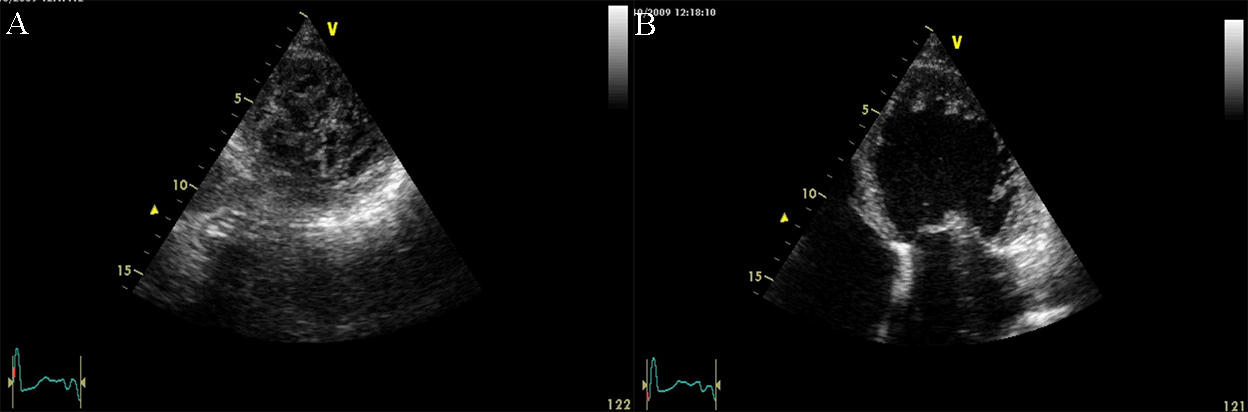

Fig. 4.Echocardiographic aspect of HCM. (A) Apical 4 chamber view systolic frame, showing increased septum thickness. (B) Apical 4 chamber view diastolic frame. (C) Parasternal long-axis view- evidence of systolic anterior motion of the mitral valve. An online video of this patient with HCM is available (Appendix Video 4).

2D echocardiography in HCM detects a septal wall thickness higher than 14 mm as

a diagnostic criterion for HCM, after excluding all the other causes of LV

hypertrophy. The severity and distribution of hypertrophy in HCM are highly

variable [23]. It may be concentric or localized (septal, apical, free LV wall,

or right ventricle hypertrophy) with or without intraventricular obstruction

(medio-ventricular, LV outflow). One pathognomonic echocardiographic feature is

the asymmetric septal hypertrophy, with a ratio of septal to the posterior wall

thickness of 1.5/1 [29]. The first echocardiographic criterion for the diagnosis

of LV hypertrophy is the LV mass obtained by M-mode and defined by an LV mass

index